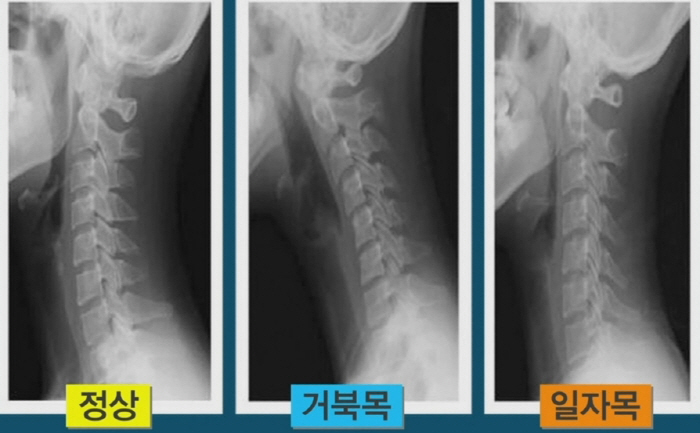

건강한 목은 c커브이예요. 하지만 컴퓨터, 스마트폰, 꼬이게된 생활습관으로 인하여 일자목이 됐을 경우, 목 뼈가 펴지며 혈관을 누르게 되기도 합니다. 이로 인하여 혈액 순환에 문제가 생기고 산소 공급이 잘 되지 않아 두통, 어지럼증, 현기증, 이명 등이 사료됩니다. 그리고 목을 눌렀을 때 두통과 현기증이 일어날 수도 있어요.

-오랜 세월 컴퓨터, 스마트폰, 독서를 거북목 자세로 하는 경우